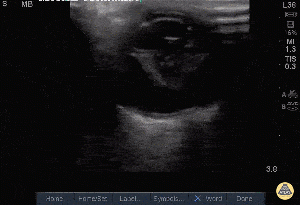

Abnormal

Abnormal Exam

A bedside ultrasound was conducted to assess for signs of retinal detachment or vitreous hemorrhage with clinical indications of left/right sided vision changes. The anterior chamber, lens, and posterior chamber of the left/right eye was identified during active movement. There was a hyperechoic flap located in the anterior chamber/swirling debris in the posterior chamber. There was sonographic evidence of retinal detachment/vitreous hemorrhage.